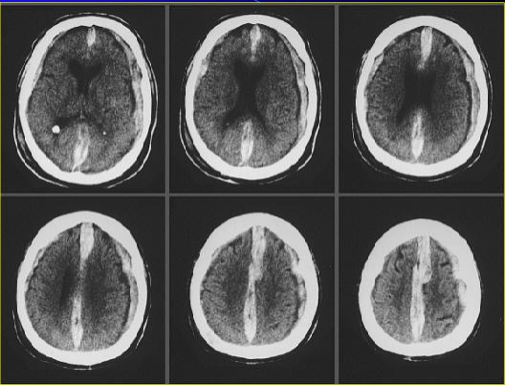

CT

left: lateral ventricles so it is very superior

right: brainstem level (the eyeballs are present)